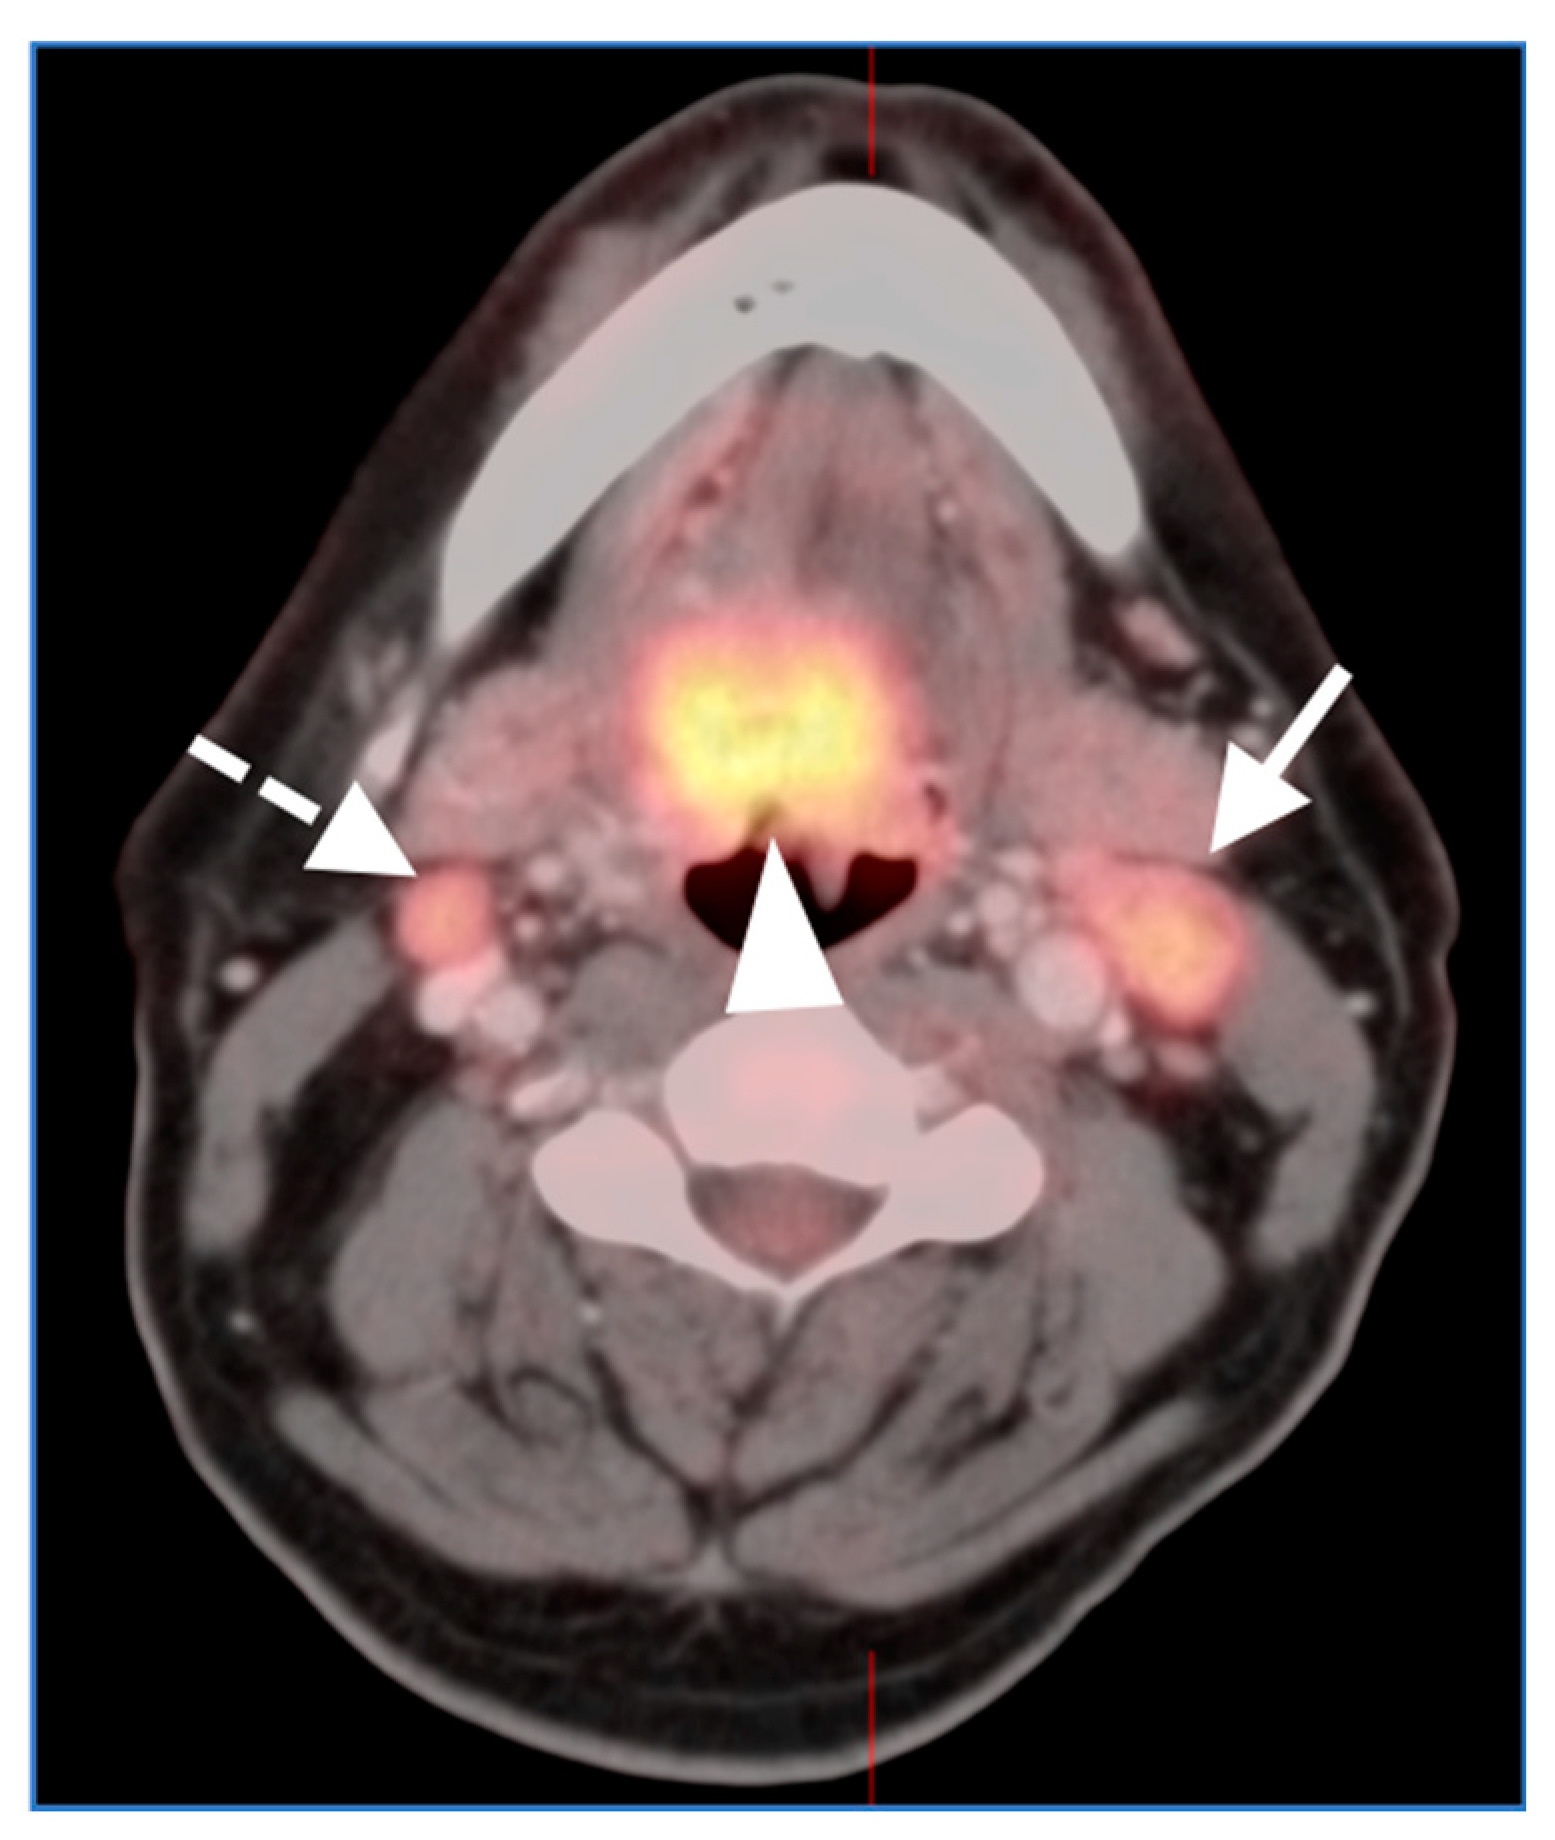

2.2. Squamous Cell Carcinoma of the Head and Neck (SCCHN)

- Oral cavity squamous cell carcinoma

- Oropharyngeal squamous cell carcinoma